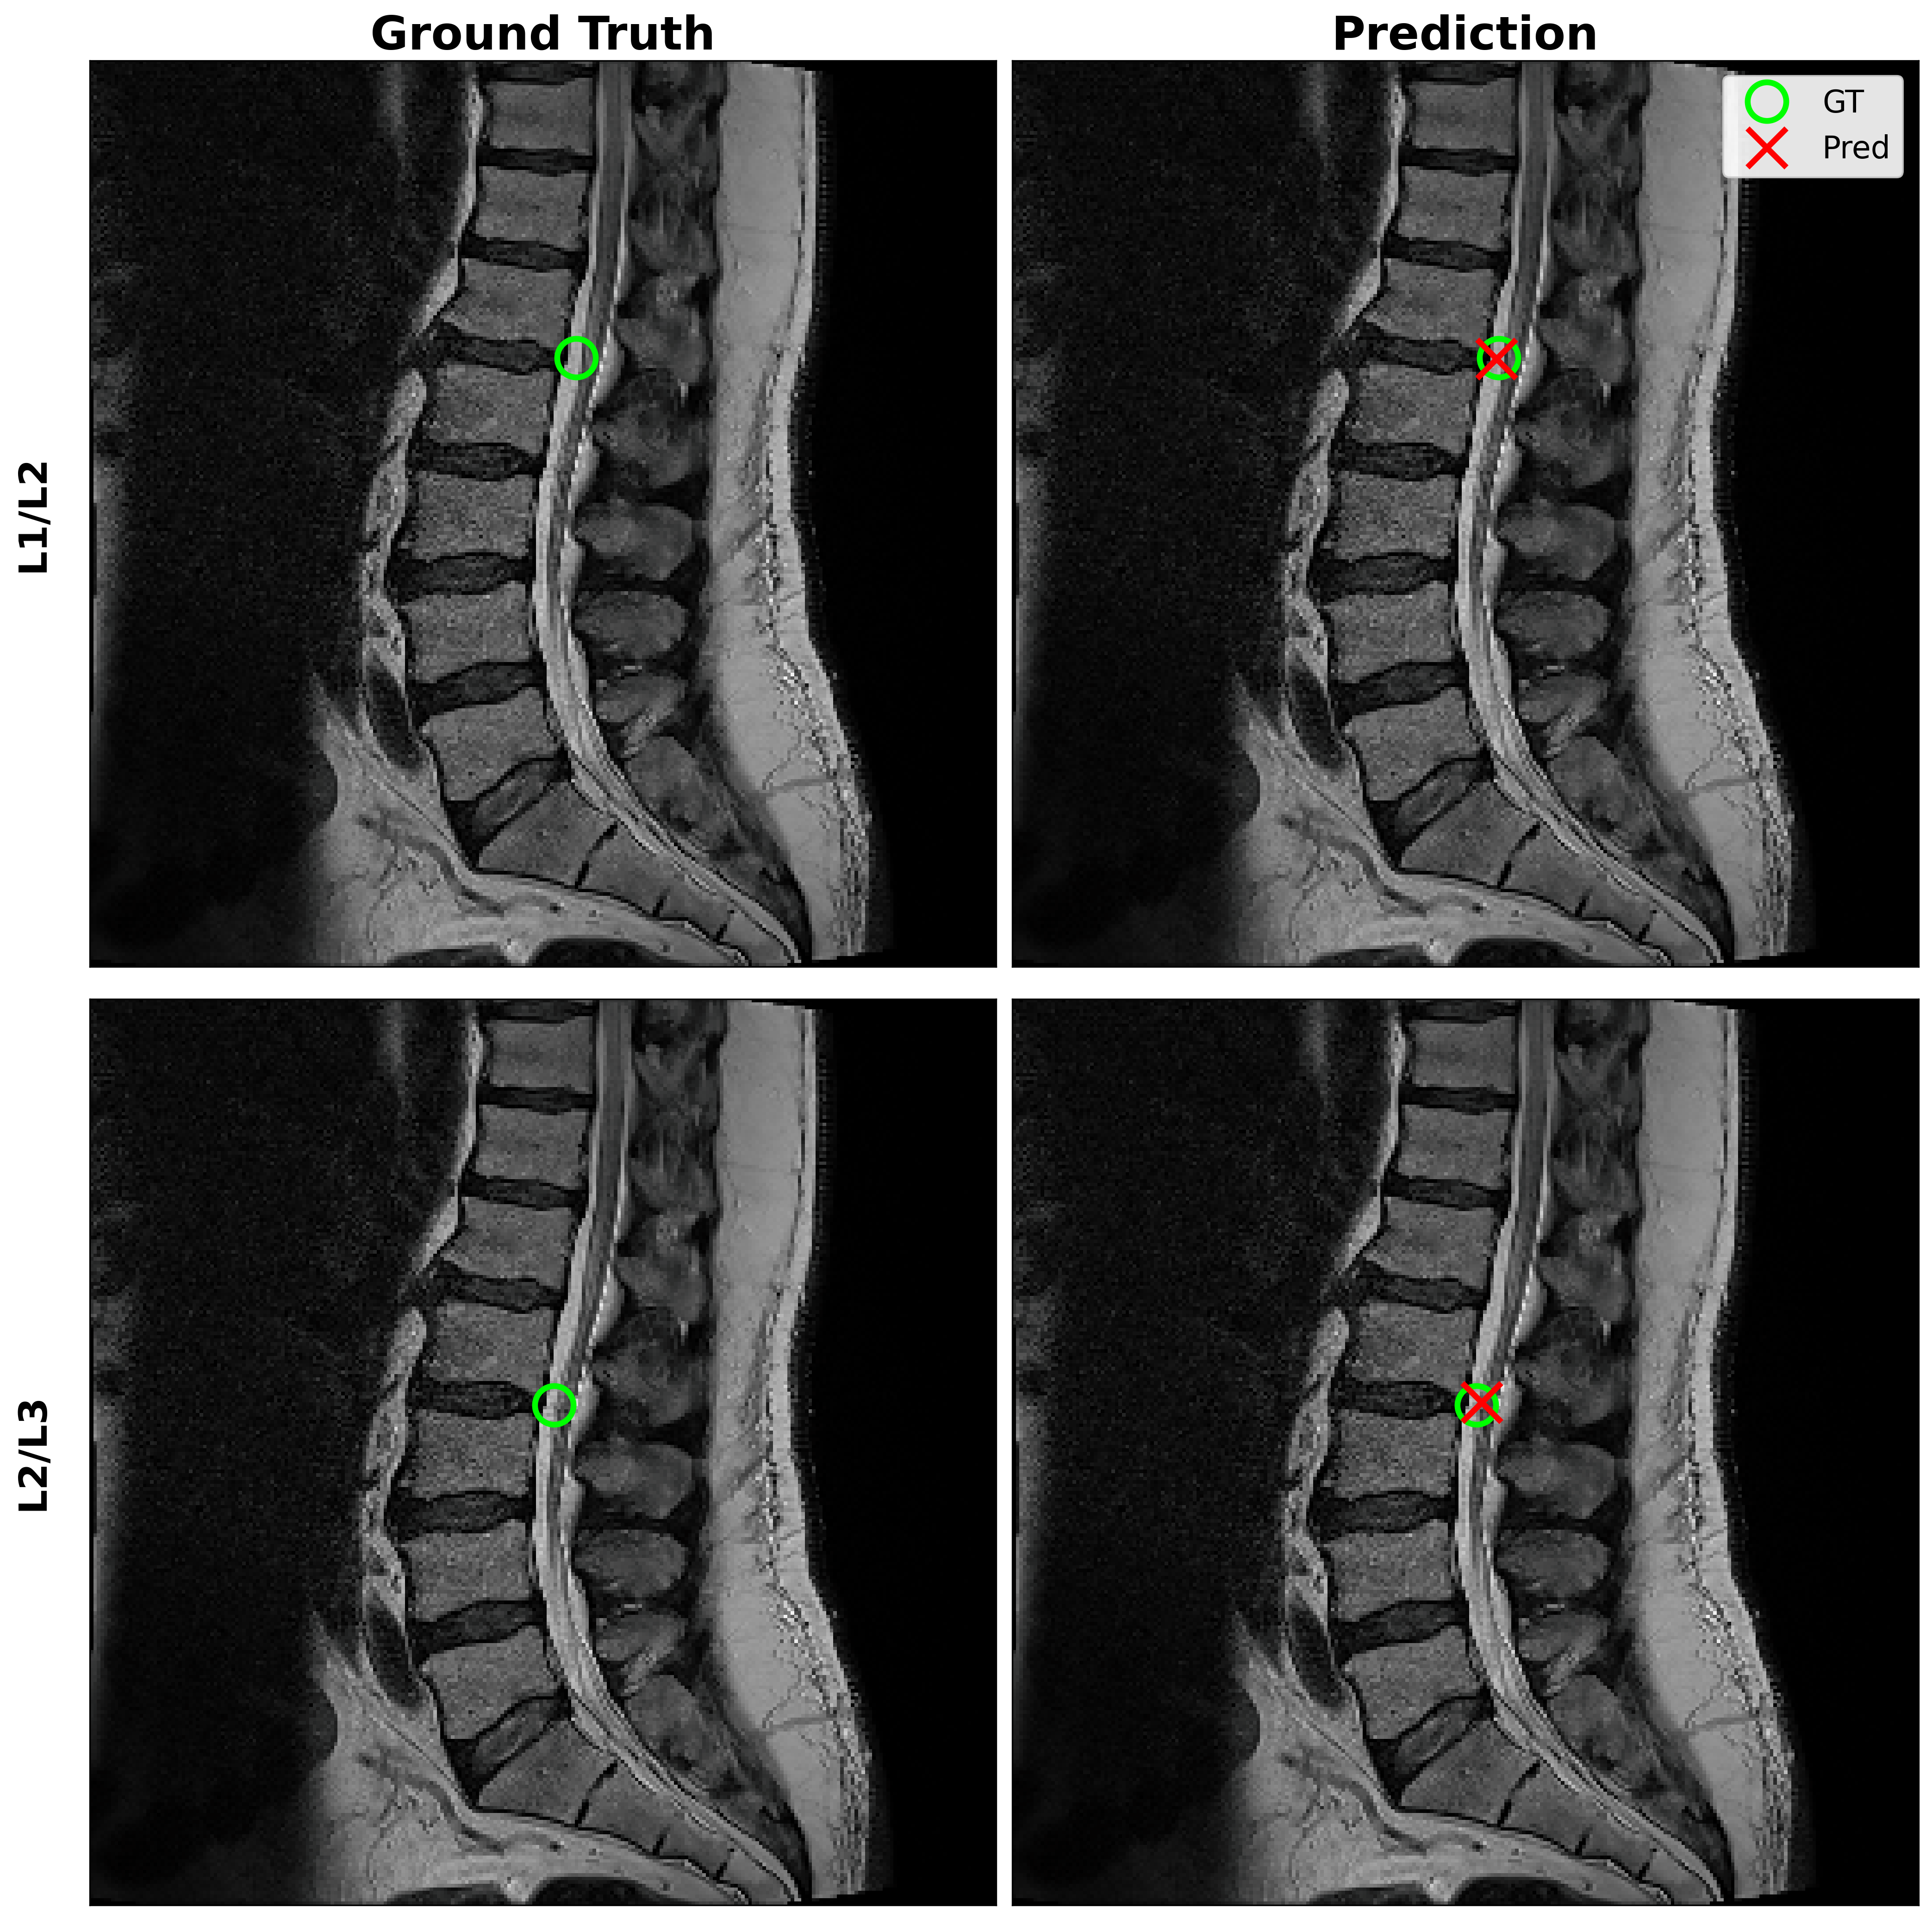

Experiments are conducted on sagittal T2-weighted lumbar spine MRI scans. For each intervertebral disc level, a single representative Region of Interest (ROI) is extracted based on the provided pathology coordinates. We extracted a 96×9696\times 96 pixel crop centered on the disc individually as illustrated in Figure 1. For pathologies located near image boundaries, constant padding is applied prior to cropping to maintain a consistent ROI size.

Refer to caption

Figure 1: Visualization of disc localization and cropping. (a) Sagittal T2-weighted lumbar spine MRI slice showing the five intervertebral disc locations (L1/L2 through L5/S1) marked with colored dots. (b) Corresponding 96×9696\times 96 pixel cropped Regions of Interest (ROIs) for each disc. Colors of the dots in (a) match the labels in (b).

To prevent data leakage across experiments, all dataset splits are performed at the disc level, ensuring that images from the same disc of the same study never appeared in both training and validation sets. Stratified splitting is then applied at the disc level based on pathology severity labels (Normal, Moderate, Severe), preserving class distribution across splits. This strategy prevents data leakage; random splitting could inflate performance due to near-identical anatomical content across splits.